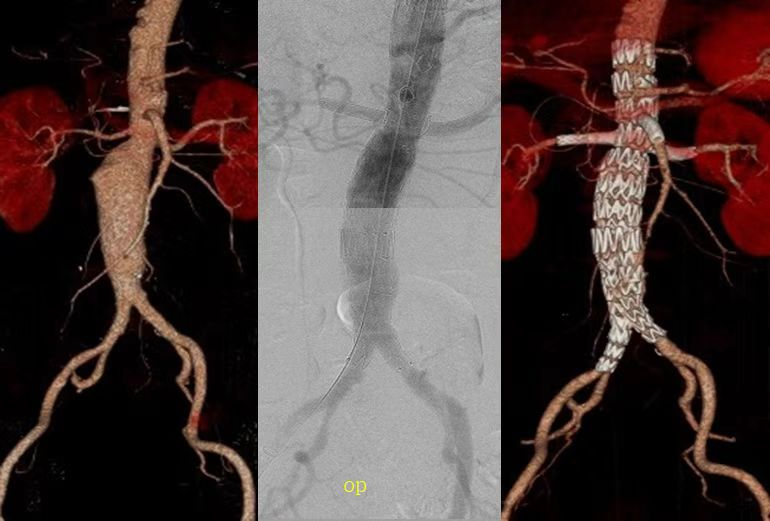

1.主动脉疾病的诊治

胸主动脉及腹主动脉瘤的腔内治疗、支架开窗及分支重建手术;

破裂腹主动脉瘤、感染腹主动脉瘤、复杂胸腹主动脉瘤的开放和腔内治疗。

胸主动脉及腹主动脉病变腔内介入及杂交手术诊疗,复杂主动脉瘤的开窗及分支支架植入,开放腹主动脉瘤重建、颈动脉内膜剥脱术,颈动脉体瘤手术,下肢急慢性动脉缺血的开放手术及介入治疗、下肢深静脉血栓及肺栓塞的一体化诊疗、内脏动脉瘤和内脏动脉缺血的介入治疗,复杂动静脉畸形的诊治等。